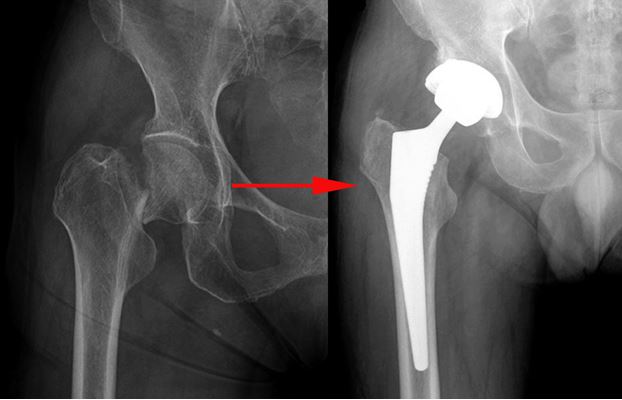

Чтобы избежать такого трагического исхода необходимо как можно быстрее после травмы «поставить больного на ноги». На помощь приходит такой метод хирургического лечения, как эндопротезирование тазобедренного сустава. Данная процедура представляет собой замену поврежденного сустава искусственным имплантом. Операция позволяет пациенту избежать инвалидности, вернув способность передвижения.

Немаловажным фактором успеха операции является качество эндопротеза. В госпитале им. акад. Н.Н. Бурденко используют только высококачественные долговечные импланты, изготовленные ведущим производителем ортопедического оборудования ZimmerBiomet.

Широкий ассортимент имплантов Zimmer Biomet позволяет подобрать эндопротез с учетом возраста пациента, его физической активности, а также характера и тяжести заболевания или травмы.

В ортопедическом отделении Главного военного клинического госпиталя им. акад. Н.Н. Бурденко вопросами эндопротезирования занимаются уже более 30 лет. Здесь выполняются операции любой категории сложности: от однополюсного эндопротезирования тазобедренного и одномыщелкового до замещения крупных дефектов костей, составляющих тазобедренный и коленный суставы с использованием «мега-протезов». Современное и высококачественное оборудование Zimmer Biomet позволяет получать высокие результаты операций и ставить на ноги даже самых тяжелых больных.